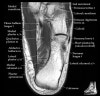

- Axial section

Axial PD fat suppression evaluates the tendons and ligaments of the ankle particularly after acute/subacute injuries. It also is sensitive to talar dome osteochondral defects. Alternatively, a T2 sequence can be used to eliminate magic angle artifact that may occur as the tendons travel around the malleolar turns.

Tibiofibular ligaments

Lateral ankle ligaments

Deltoid and spling ligaments

Tendon(Achilles, Medial, Lateral, Anterior)